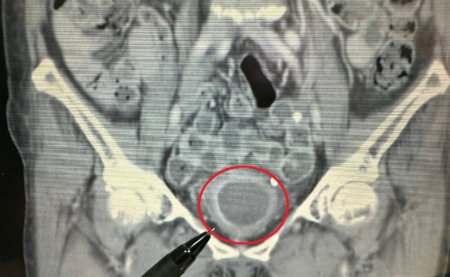

進一步安排靜脈注射腎盂攝影,顯示在膀胱內有大片陰影,續以膀胱鏡檢查,發現膀胱內有一個約7×6公分的巨大腫瘤。所幸,經醫師安排「經尿道膀胱腫瘤刮除手術」後,順利清除腫瘤,也成功保留膀胱,目前恢復良好並定期回診追蹤。

大千綜合醫院泌尿科醫師陸兆明表示,此位病人的膀胱腫瘤體積頗大,已占據未漲尿時的膀胱將近1/2空間,但因為腫瘤細胞尚未侵犯到膀胱外圍,也沒有骨盆淋巴結轉移的情況,因此適用「經尿道膀胱腫瘤刮除手術」來處理腫瘤。此手術透過膀胱內視鏡,由尿道進入膀胱來逐步刮除腫瘤,不僅可得到足夠的檢體,來檢查癌細胞有無侵犯深層肌肉,並將肉眼可見的病灶加以切除;同時,病人腹部無傷口,且可保留膀胱,繼續保有儲尿和排尿的功能,不需另裝人工膀胱,就能維持正常生活品質。另外,病人手術後恢復快、併發症少、安全性較高,對於初期膀胱癌的病人而言是一適合的治療選擇。